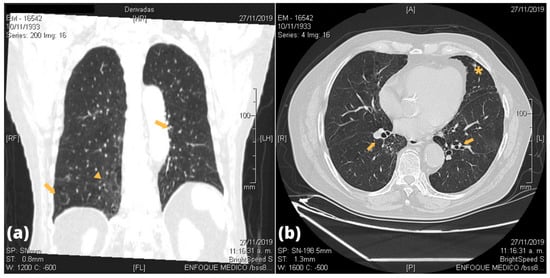

| Patients | Bronchial Lesion | Alveolar Lesion | Parenchymal Lesion | Pleural Lesion |

|---|---|---|---|---|

| P1 | None | None | Scarce right inferior fibrous sequelae tracts | None |

| P2 | Bilateral tubular bronchiectasis | None | Bilateral GGO; scarce right inferior fibrous retractile tracts | None |

| P3 | Bilateral varicose bronchiectasis | None | None | None |

| P4 | None | None | Bilateral apical fibrous retractile tracts | Bilateral apical pleural thickening |

| P5 | Right medial bronchiectasis | None | Bilateral inferior GGO; bilateral apical fibrous retractile tracts; right medial air cyst | Bilateral apical pleural thickening |

| P6 | Right medial and left inferior bronchiectasis | None | Bilateral inferior fibrous retractile tracts; right apical interstitial infiltrate | None |

| P7 | Left atelectasis | None | Bilateral inferior interstitial infiltrate | None |

| P8 | Bilateral cylindrical hilio-perihiliar bronchiectasis; laminar atelectasis | None | Bilateral apical fibrous retractile tracts | Right apical pleural thickening |

| P9 | Bilateral tubular bronchiectasis | None | Bilateral GGO with fibrous tracts | None |

| P11 | Right medial varicose bronchiectasis | None | Bilateral inferior GGO and interlobular septal interstitial thickening; bilateral apical thick fibrous sequelae tracts | Bilateral apical pleural thickening |

| P12 | Right tubular bronchiectasis | None | Bilateral inferior opacities and fibro retractable tracts | Bilateral pleural thickening |

| P13 | Bilateral tubular and varicose bronchiectasis | None | Right inferior GGO; bilateral inferior intra- and interlobular thickening | None |

| P14 | None | None | None | None |

| P15 | None | None | Subpleural infiltrate | None |

| Radiological Lung Lesion | Frequency |

|---|---|

| Lobe compromise | |

| Lower lobe: RL, LF | 10/14, 9/14 |

| Medial lobe: RL | 7/14 |

| Upper lobe: RL, LF | 7/14, 5/14 |

| Bronchial lesions | |

| Bronchiectasis | 9/14 |

| Bilateral | 5/9 |

| Atelectasis | 2/14 |

| Alveolar damage | 0/14 |

| Parenchymal damage | |

| GGO/infiltrates | 7/14 |

| Fibro-retractable tracts | 10/14 |

| Bilateral pleural thickness | 5/14 |